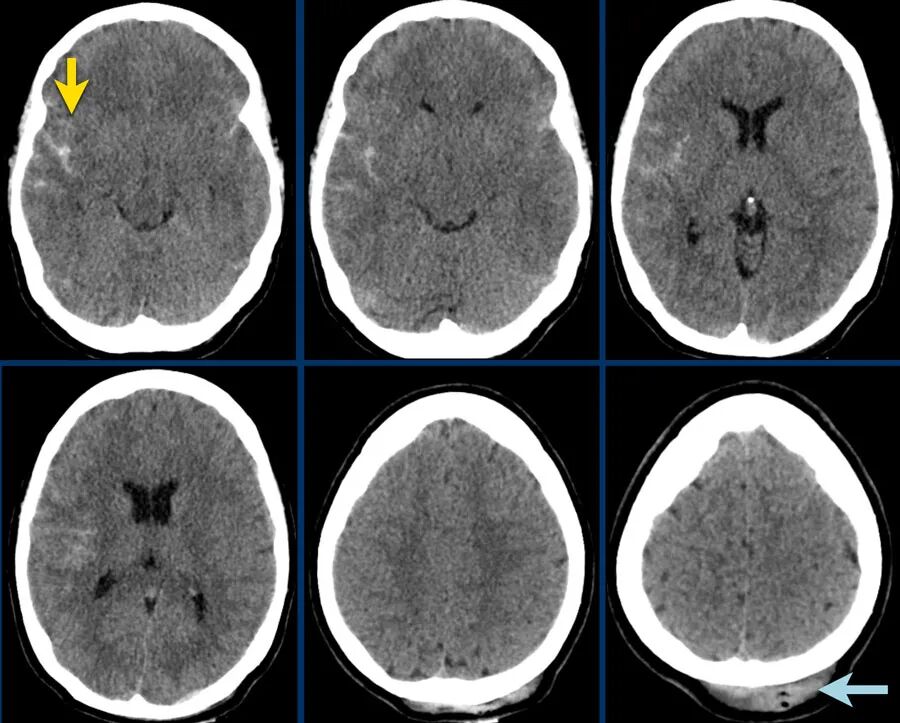

蛛网膜下腔出血

下图显示了外侧裂蛛网膜下腔(黄色箭头)的高密度血液。

注意右侧枕部的皮下出血(蓝色箭头)。

这是一种对冲伤。

弥漫性轴索损伤

下图 一位46岁的男子骑摩托车时受伤。

瞳孔无反应性,瞳孔扩张。

CT:额叶点状出血。

继续做核磁共振成像